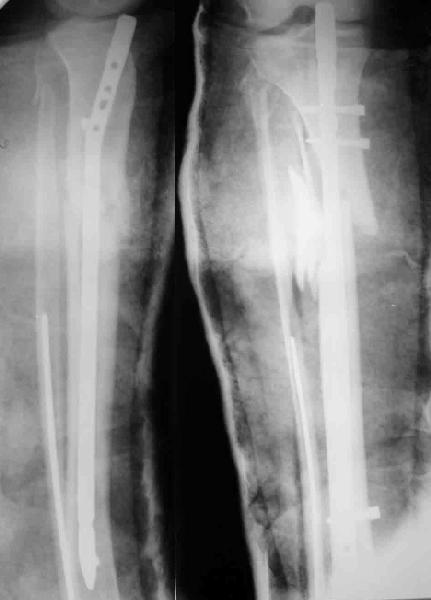

У меня складывается впечатление, что пластина сломалась в зоне несращения б.б кости, малоберцовая сраслась в дистальной части, в области шейки м.б. сращения не видно,видимо, это и обуславливает патологическую подвижность

Мне кажется, что коль скоро фиксатор не выполняет своей роли, то зачем его оставлять.

Но думается, что окончательное решение должно быть принято интраоперационно после удаления пластины, насколько жизнеспособно выглядит промежуточный фрагмент, вполне возможно, что в процессе репозиции фрагментов при повторной

хирургии мобилизация промежуточного фрагмента привела к нарушению его кровоснабжения и ждать сращения от аваскулярной кости не приходится.

Все-таки за 5 месяцев голень должна срастаться при нормальных условиях. Если промежуточный фрагмент не отличается по своим свойствам от прилежащих фрагментов, то можно фикмровать и рассверливаемым стержнем без дополнительного забора аутокости. Если же отличия очевидны - костная пластика из крыла подвздошной кости и фиксация либо в аппарате , либо в гипсовой повязке.